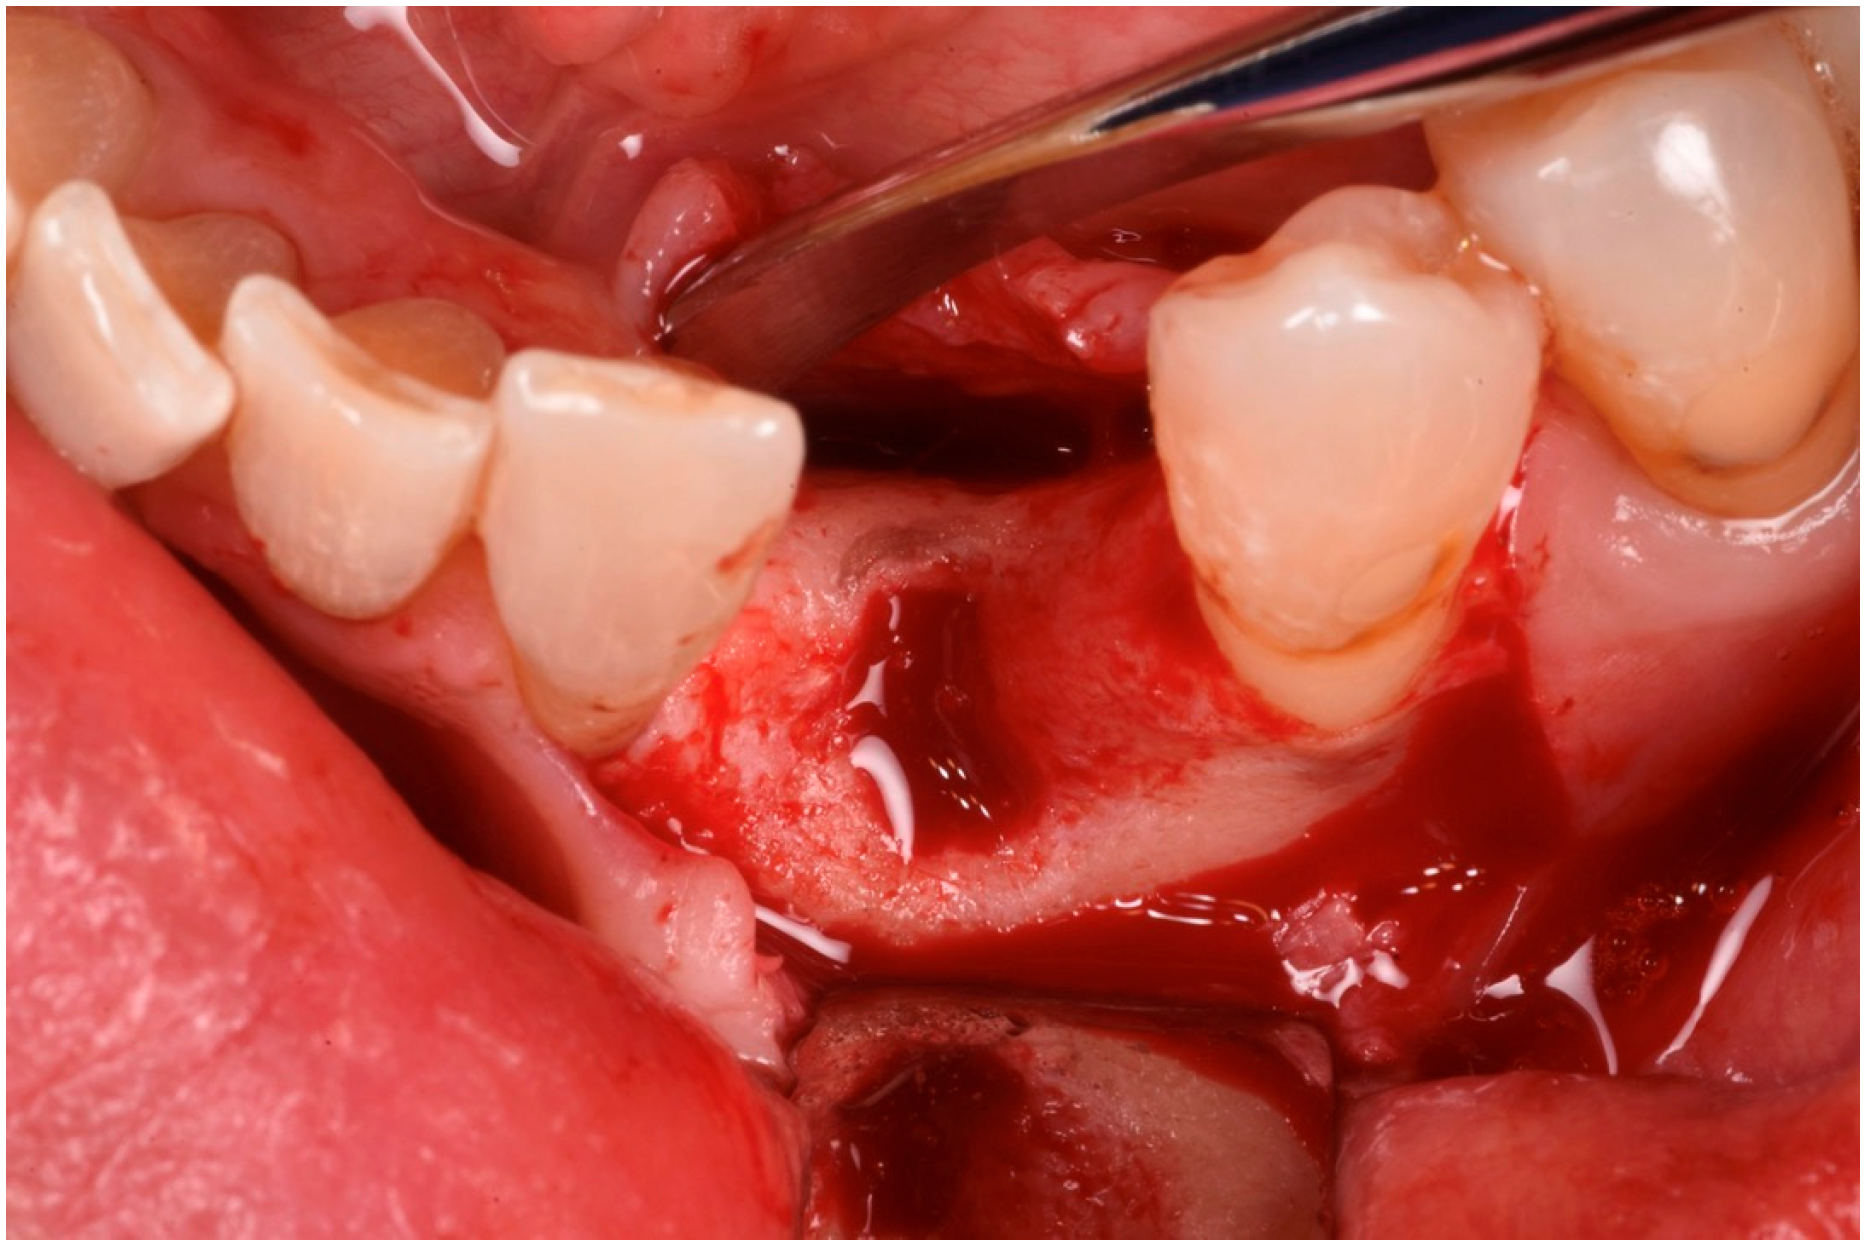

The patient was anesthetized with articaine 1:200,000. A flap was designed to extend from the distal aspect of the lateral incisor to the distal of the first bicuspid. In this case, only one releasing incision was made distal to the bicuspid to provide greater flexibility at the mesial aspect, where bone loss was more advanced. A full-thickness buccal and lingual flap was elevated to expose the 3D lesion. The mesial–distal component of the defect measured 13 mm, with a significant portion of the buccal plate completely missing (Figure 4). The vertical component of the defect comprised 9 mm of suprabony component and 4 mm of infrabony component (Figure 5). The horizontal bone loss between the lingual and buccal walls was measured at 8 mm (Figure 6).

The blood clot was collected from the wound area and mixed with collagenated equine bone granules and autogenous bone scraped from the lingual side of the defect, along with a few drops of fibrin glue (FG) (Figure 7). This mixture ensured that the graft was both malleable and sticky, allowing it to adhere effectively to the base of the defect. The recipient site was prepared using a small round bur to create intramarrow penetrations, which facilitated additional bleeding and introduced mesenchymal cells from the marrow spaces (Figure 8). In this case, two different thicknesses of FCS were used: the thicker one (0.9 mm) was applied to restore the missing buccal plate, while a thinner FCS (0.5 mm) was utilized to protect the occlusal aspect of the defect and to seal the graft underneath (Figure 9 and Figure 10).

Figure 4. Mesial–distal defect measuring 13 mm, with a significant portion of the buccal plate absent.

Figure 5. Vertical bone defect measuring 9 mm.

Figure 6. Occlusal view of the bone defect.